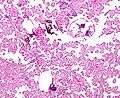

Micrograph of a choroid plexus papilloma. H&E stain.